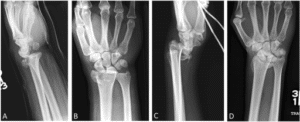

Reduction of the Fracture...

- Consider IV regional block (Bier’s Block) when reducing in the ED, ‘Gas and Air’ is not suitable on its own for fracture reduction (2).

- Following reduction and immobilization with back slab plaster, re-image to assess reduction (see ‘Radiographic Criteria’).

If fracture is dorsally displaced, but requires surgery, offer…

- K-wire fixation if…

- There is no intra-articular involvement OR

- Displacement of radial-carpel joint can be reduced under closed manipulation (2).

- Open reduction and internal fixation (ORIF) if…

- Reduction of the joint surface is not possible under closed manipulation (2).